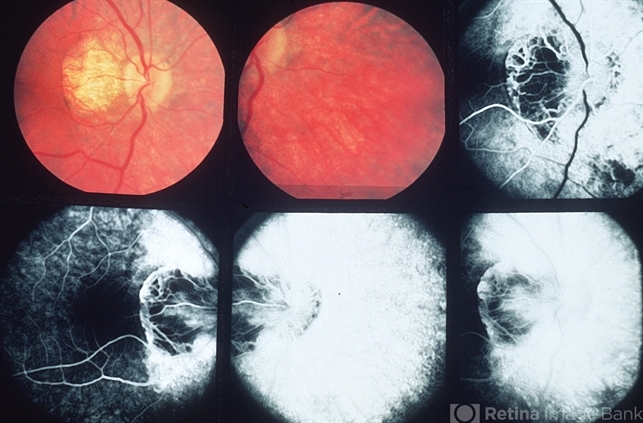

By Howard Schatz, MD

- inflammation, retinitis pigmentosa (RP) dystrophy

- 30-year-old white female, 20/30 periphery and posterior RP dystrophy.